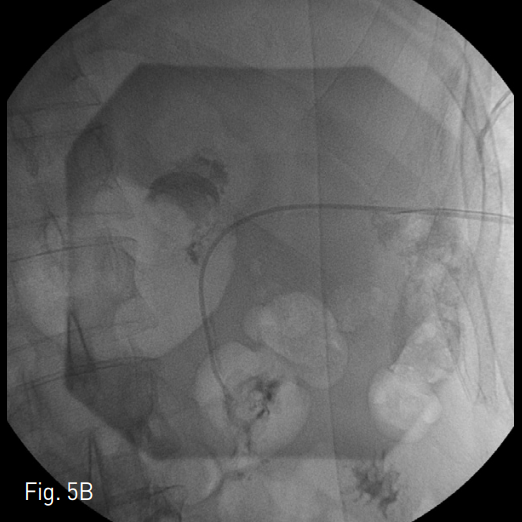

Fig. 5

Fistula between fluid cavity and jejunum was noted (A). Successful navigation to fistula tract was done with 0.035inch hydrophilic guide wire and 5 Fr KMP catheter (Cook, Bloomington, IN, USA) (B). Controlled fistula tract was embolized with 4mm Tornado (Cook, Blooming ton, IN, USA) and Histoacryl (B. Braun, Melsungen, Germany), Lipiodol Ultra Fluride (Guerbet, Roissy, France) mixture. Post-embolization tubogram showed no demonstation of previous fistula. Nelaton catheter was deployed to formation of con trolled fistula (C). 1 week later, bedside removal of Nelaton catheter was done.